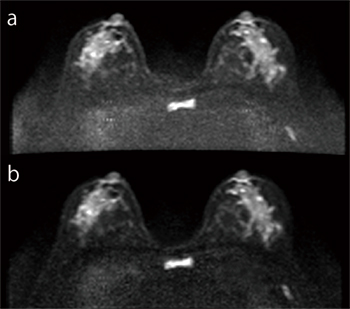

通常,SNRを向上させるための加算(NSA)を行うが,拡散強調画像(DWI)で印加するMPG(motion probing gradient)パルスは非常に大きいため位相変化が大きく,従来の絶対値加算では加算効果が期待できない(図2 a)。そこで,MPGパルスを印加した画像の加算処理を,従来の絶対値加算から複素加算に変更することで,組織の信号を保ちつつノイズ領域の信号のみを低減してSNRを向上させることが可能である(図2 b)。

図2 H-sinc併用DWI(b1000s/mm2)

a:絶対値加算画像

b:複素加算画像

2.7mm×2.0mm×5mm reso,

28slice,2min31s